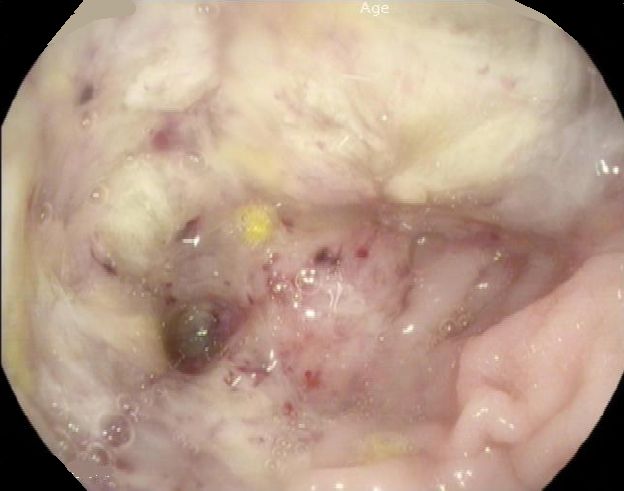

Anastomosen - Rezidiv 66-jähriger Mann, der vor 6 Monaten ein Karzinom der rechten Colonflexur hatte. Postoperativ pT3d pN2a (6/23)cM1a(PUL) L1 V0 Pn0. Adjuvant Bevacizumab/FOLFIRI. Jetzt endoskopisch Tumornachweis an der Anastomose.